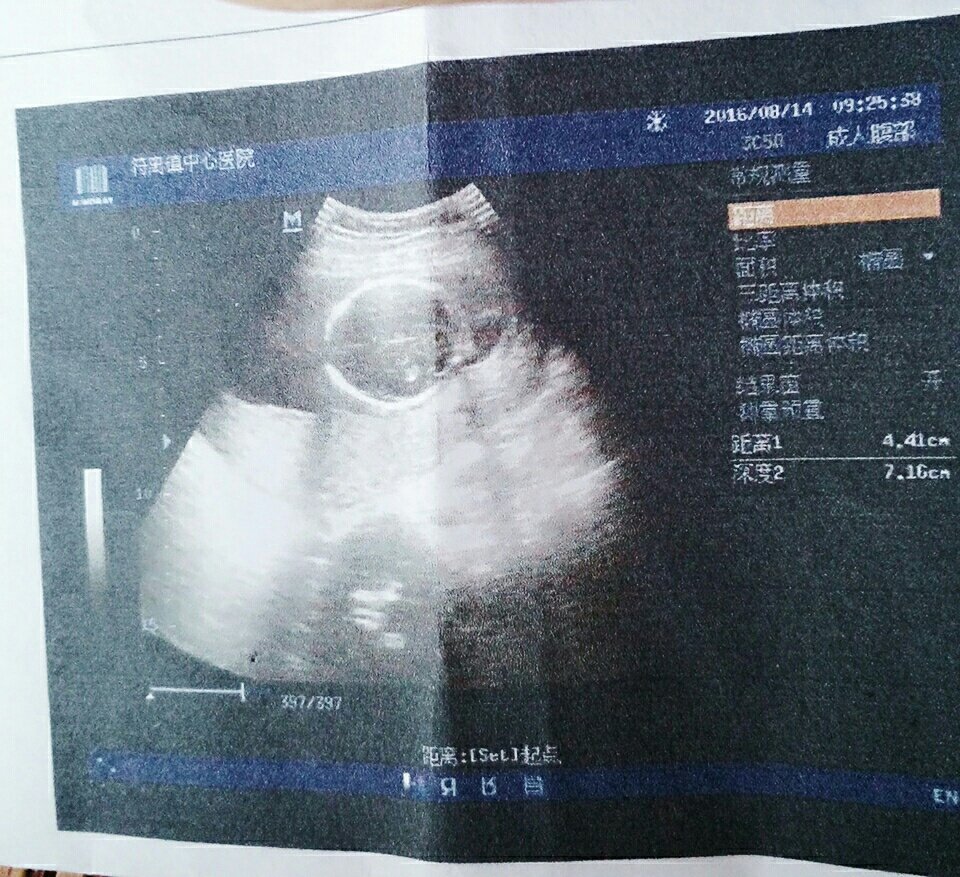

没拍下面的数据,亲们看看图像,觉得是男宝还是女宝呢,宝妈只是很好奇